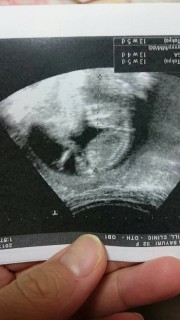

写真:13w4d:Mihoさん

人間らしい体になっていて 体育座りしていて 腕が長いねと言われました笑

性別はまだわかりませんが 元気に動いている姿を見せてくれました! 4歳のお兄ちゃんに見せると 可愛いと言ってくれて嬉しかったです